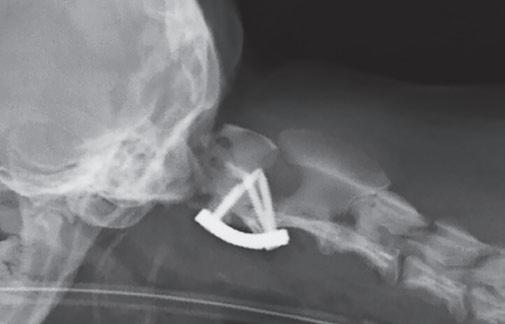

Tratamiento quirúrgico de la subluxación atlantoaxial 30

• Tratamiento quirúrgico de la subluxación atlantoaxial